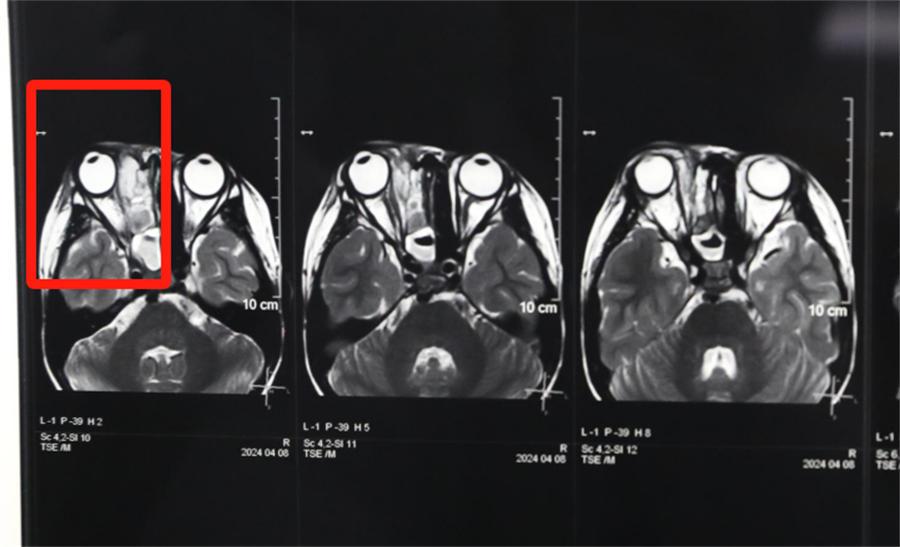

3岁男童小壮(化名)在出生后就出现左侧鼻子堵,一直流白色胶冻样鼻涕。三年来,家长反复带他去成人医院看病,每次都诊断为鼻炎,怎么用药都没治好,这也就成了一家人的烦心事。凑巧的是,前几天孩子把一粒黄豆塞进了左侧鼻孔,家长赶忙带他来到德州扑克游戏网 ,医生顺利取出了黄豆,并做了儿童电子鼻咽镜检查,这才发现了孩子左侧鼻子一直堵塞的真正原因——先天性后鼻孔闭锁。

孩子左侧鼻腔3年来没有通气,鼻腔的发育受到了严重影响,甚至部分结构出现了一定程度的萎缩,并患有严重的鼻窦炎。杨小健副院长认真分析了孩子的病情,认为应该尽快手术治疗。

考虑患儿低龄,杨小健副院长为他做了鼻内镜下后鼻孔成形术,麻醉科主任全程保驾护航,手术非常成功。术后第二天,孩子高兴地告诉妈妈,“我的鼻子终于能通气了”。困扰一家人三年的难题得到解决,孩子的家长高兴万分。